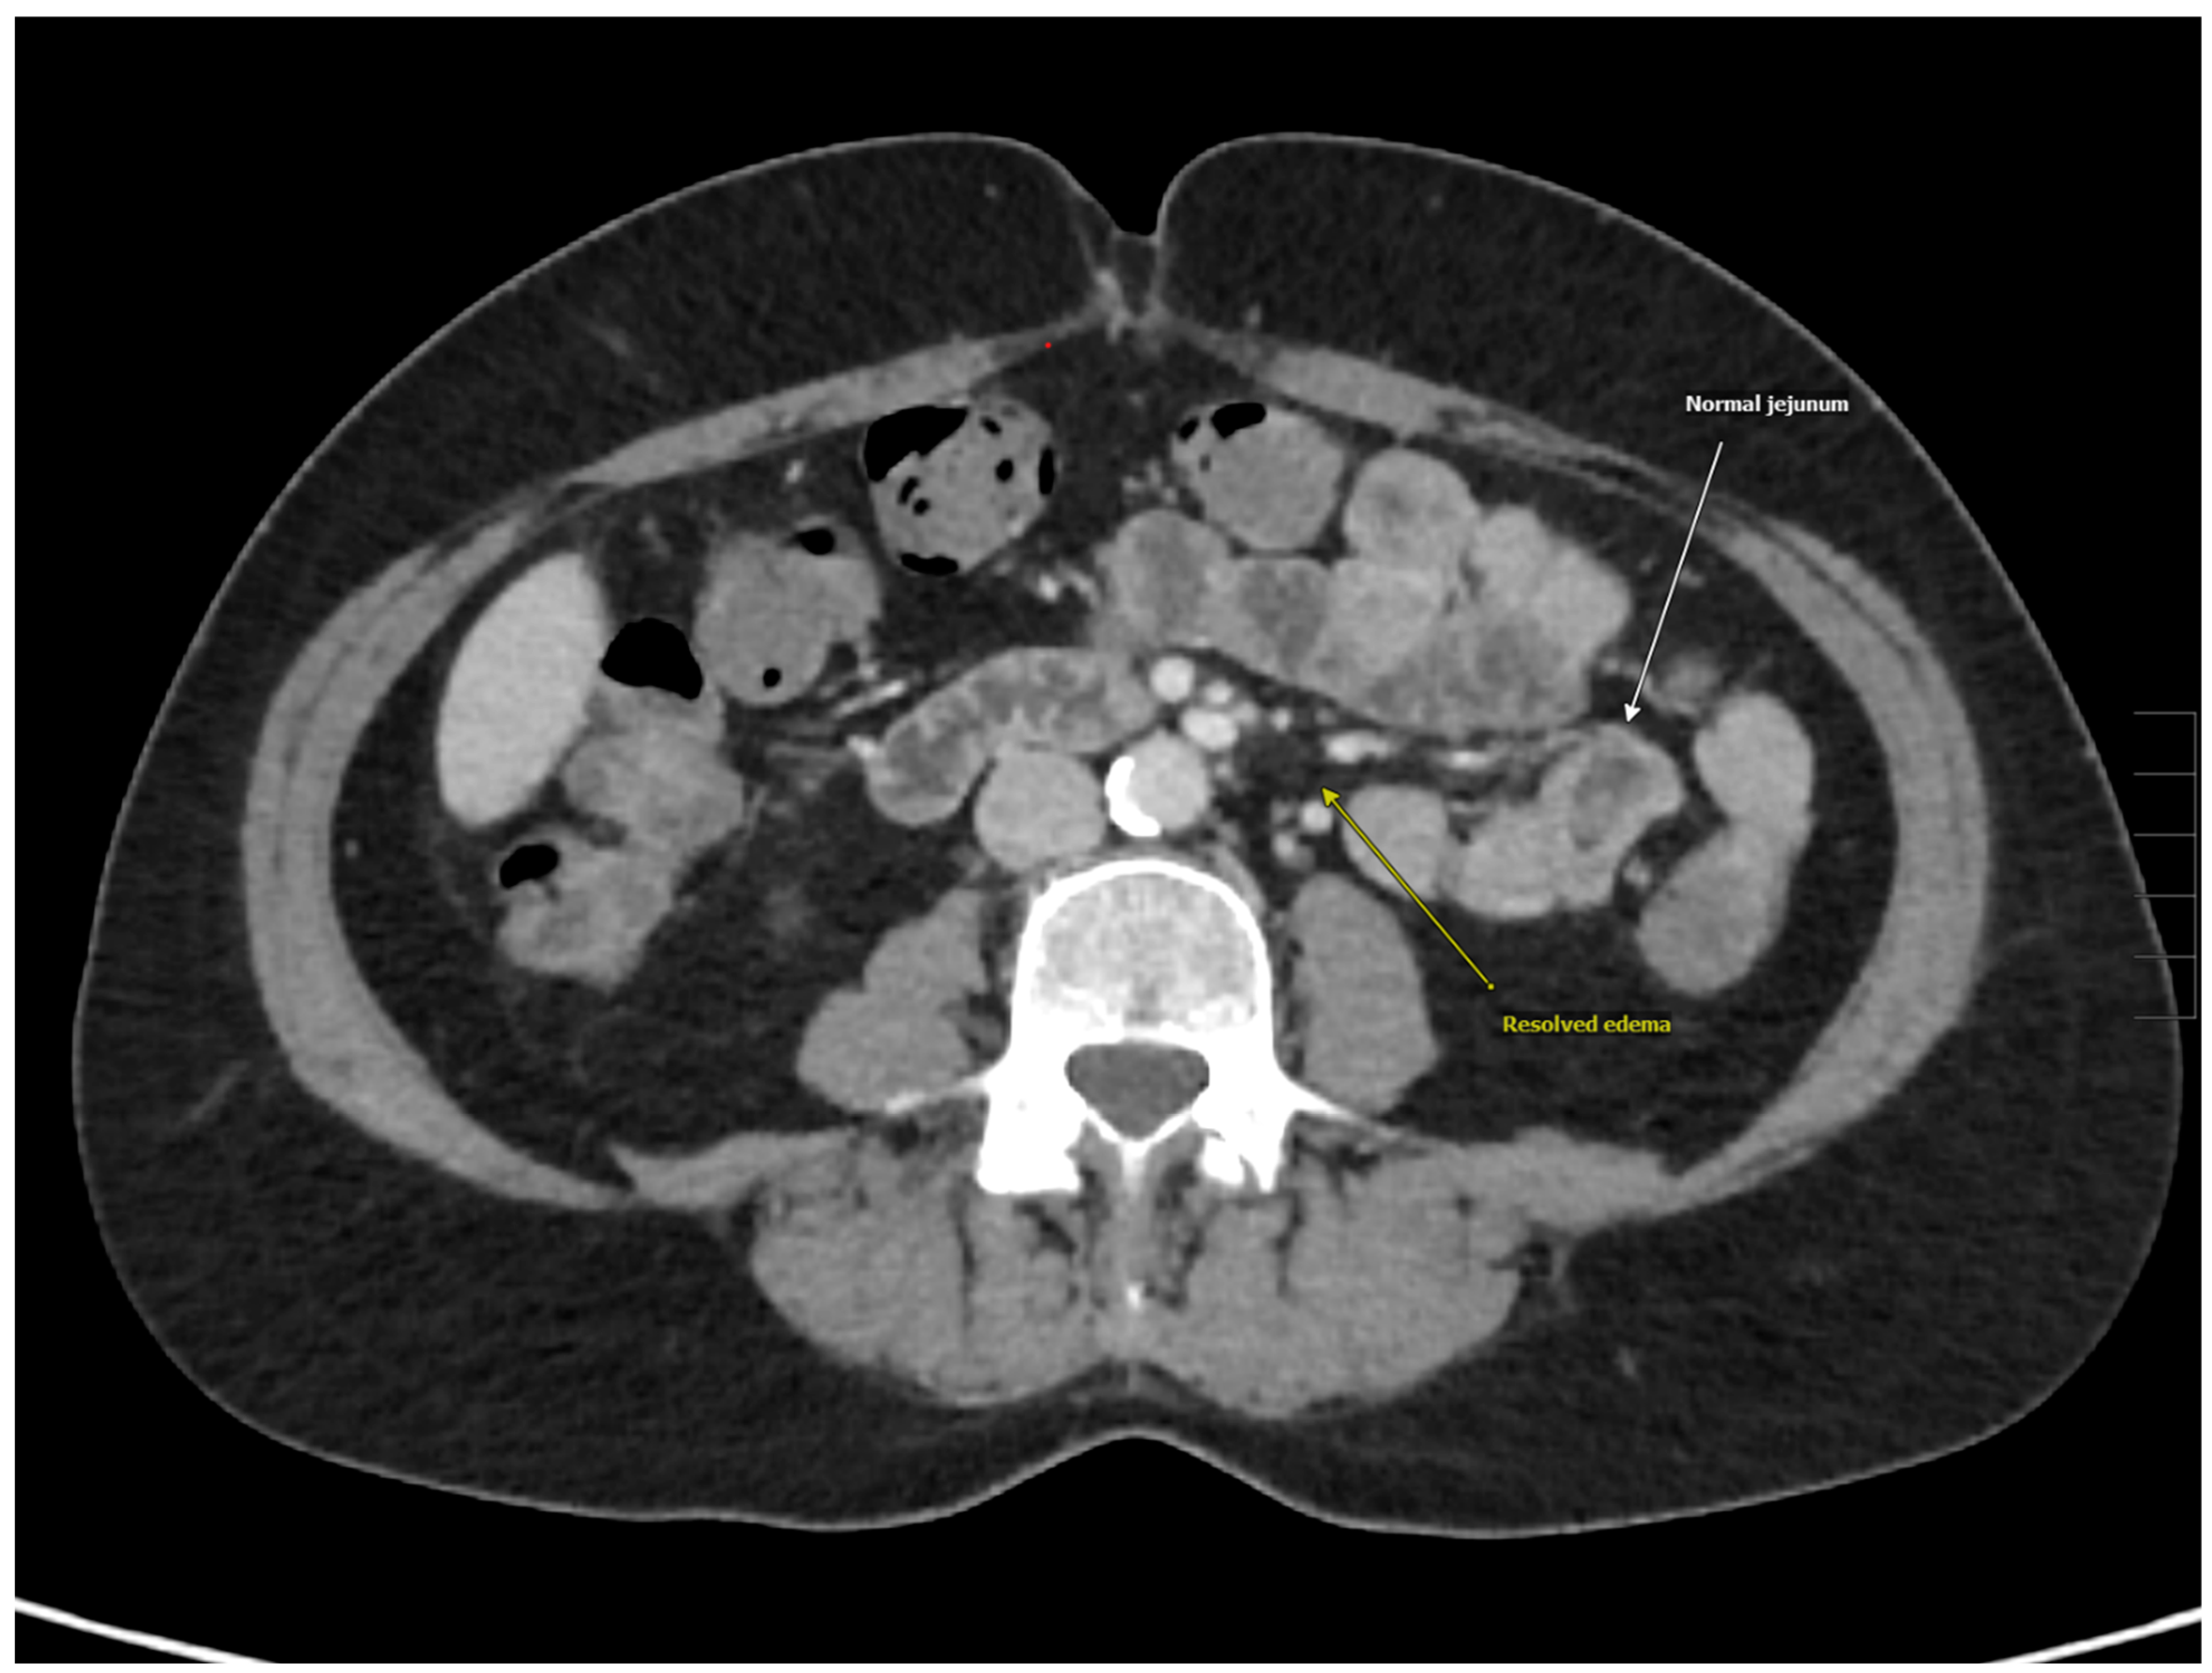

| CTAP | Pancolitis, ileitis, and peri-appendiceal stranding with prominent right lower quadrant mesenteric lymph nodes |

| MRI | Inflammation of the duodenum, jejunum, and colon |